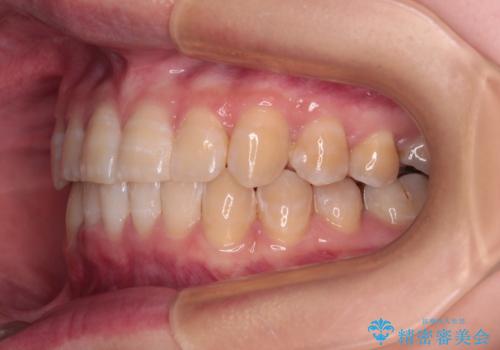

- 下顎の八重歯を気にして来院された患者様です。

マウスピース矯正でもワイヤー矯正でも対応可能であり、マウスピースによる治療を希望されたため、インビザラインを用いることとしました。

下顎前歯にデコボコが集中していたため、顎間ゴムによる後方移動とIPR(歯と歯の間を削ること)により歯列を整えることとしました。

下顎前歯のデコボコが集中しており、奥歯の咬み合わせは、上顎に対して下顎が前方位にある状態でした。下顎の歯列を後方へ移動させる治療はインビザラインの得意とするところですので、1年程度で無事に治療を終えることができました。